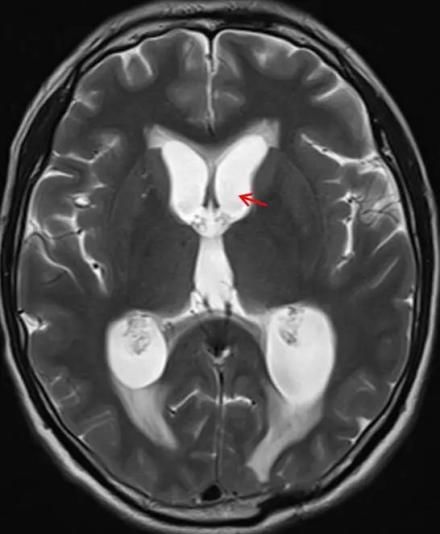

肺癌是一种高发的恶性肿瘤,即使经过手术治疗,也存在一定的复发和转移风险。其中,脑转移是肺癌常见的远处转移之一,严重影响患者的生活质量和生存期。那么,肺癌手术后多久会脑转移,转移了怎么治疗好呢?

肺癌手术后脑转移的时间因个体差异、肿瘤类型、分期、治疗方式等多种因素而异。一些患者可能在手术后不久就出现脑转移,而另一些患者则可能在数年后才出现。因此,肺癌患者和家属需要密切关注病情的变化,定期进行复查和检查,以便及时发现和处理脑转移。

当肺癌患者出现脑转移时,治疗方案需要综合考虑患者的病情、身体状况、脑转移的程度和位置等多种因素。常见的治疗方法包括手术、放疗、化疗和中医治疗等。